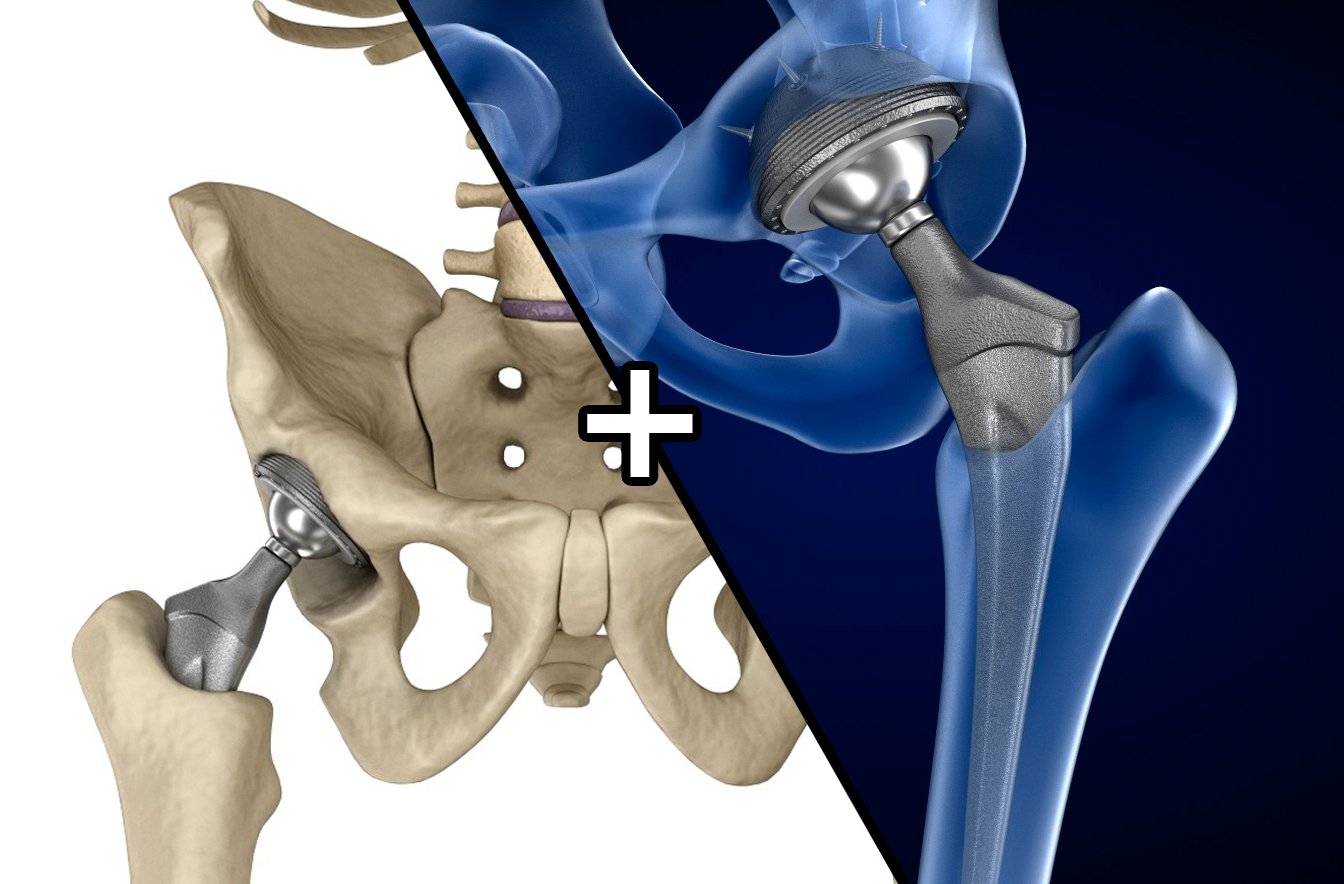

Эндопротезирование тазобедренного сустава: фото и схемы